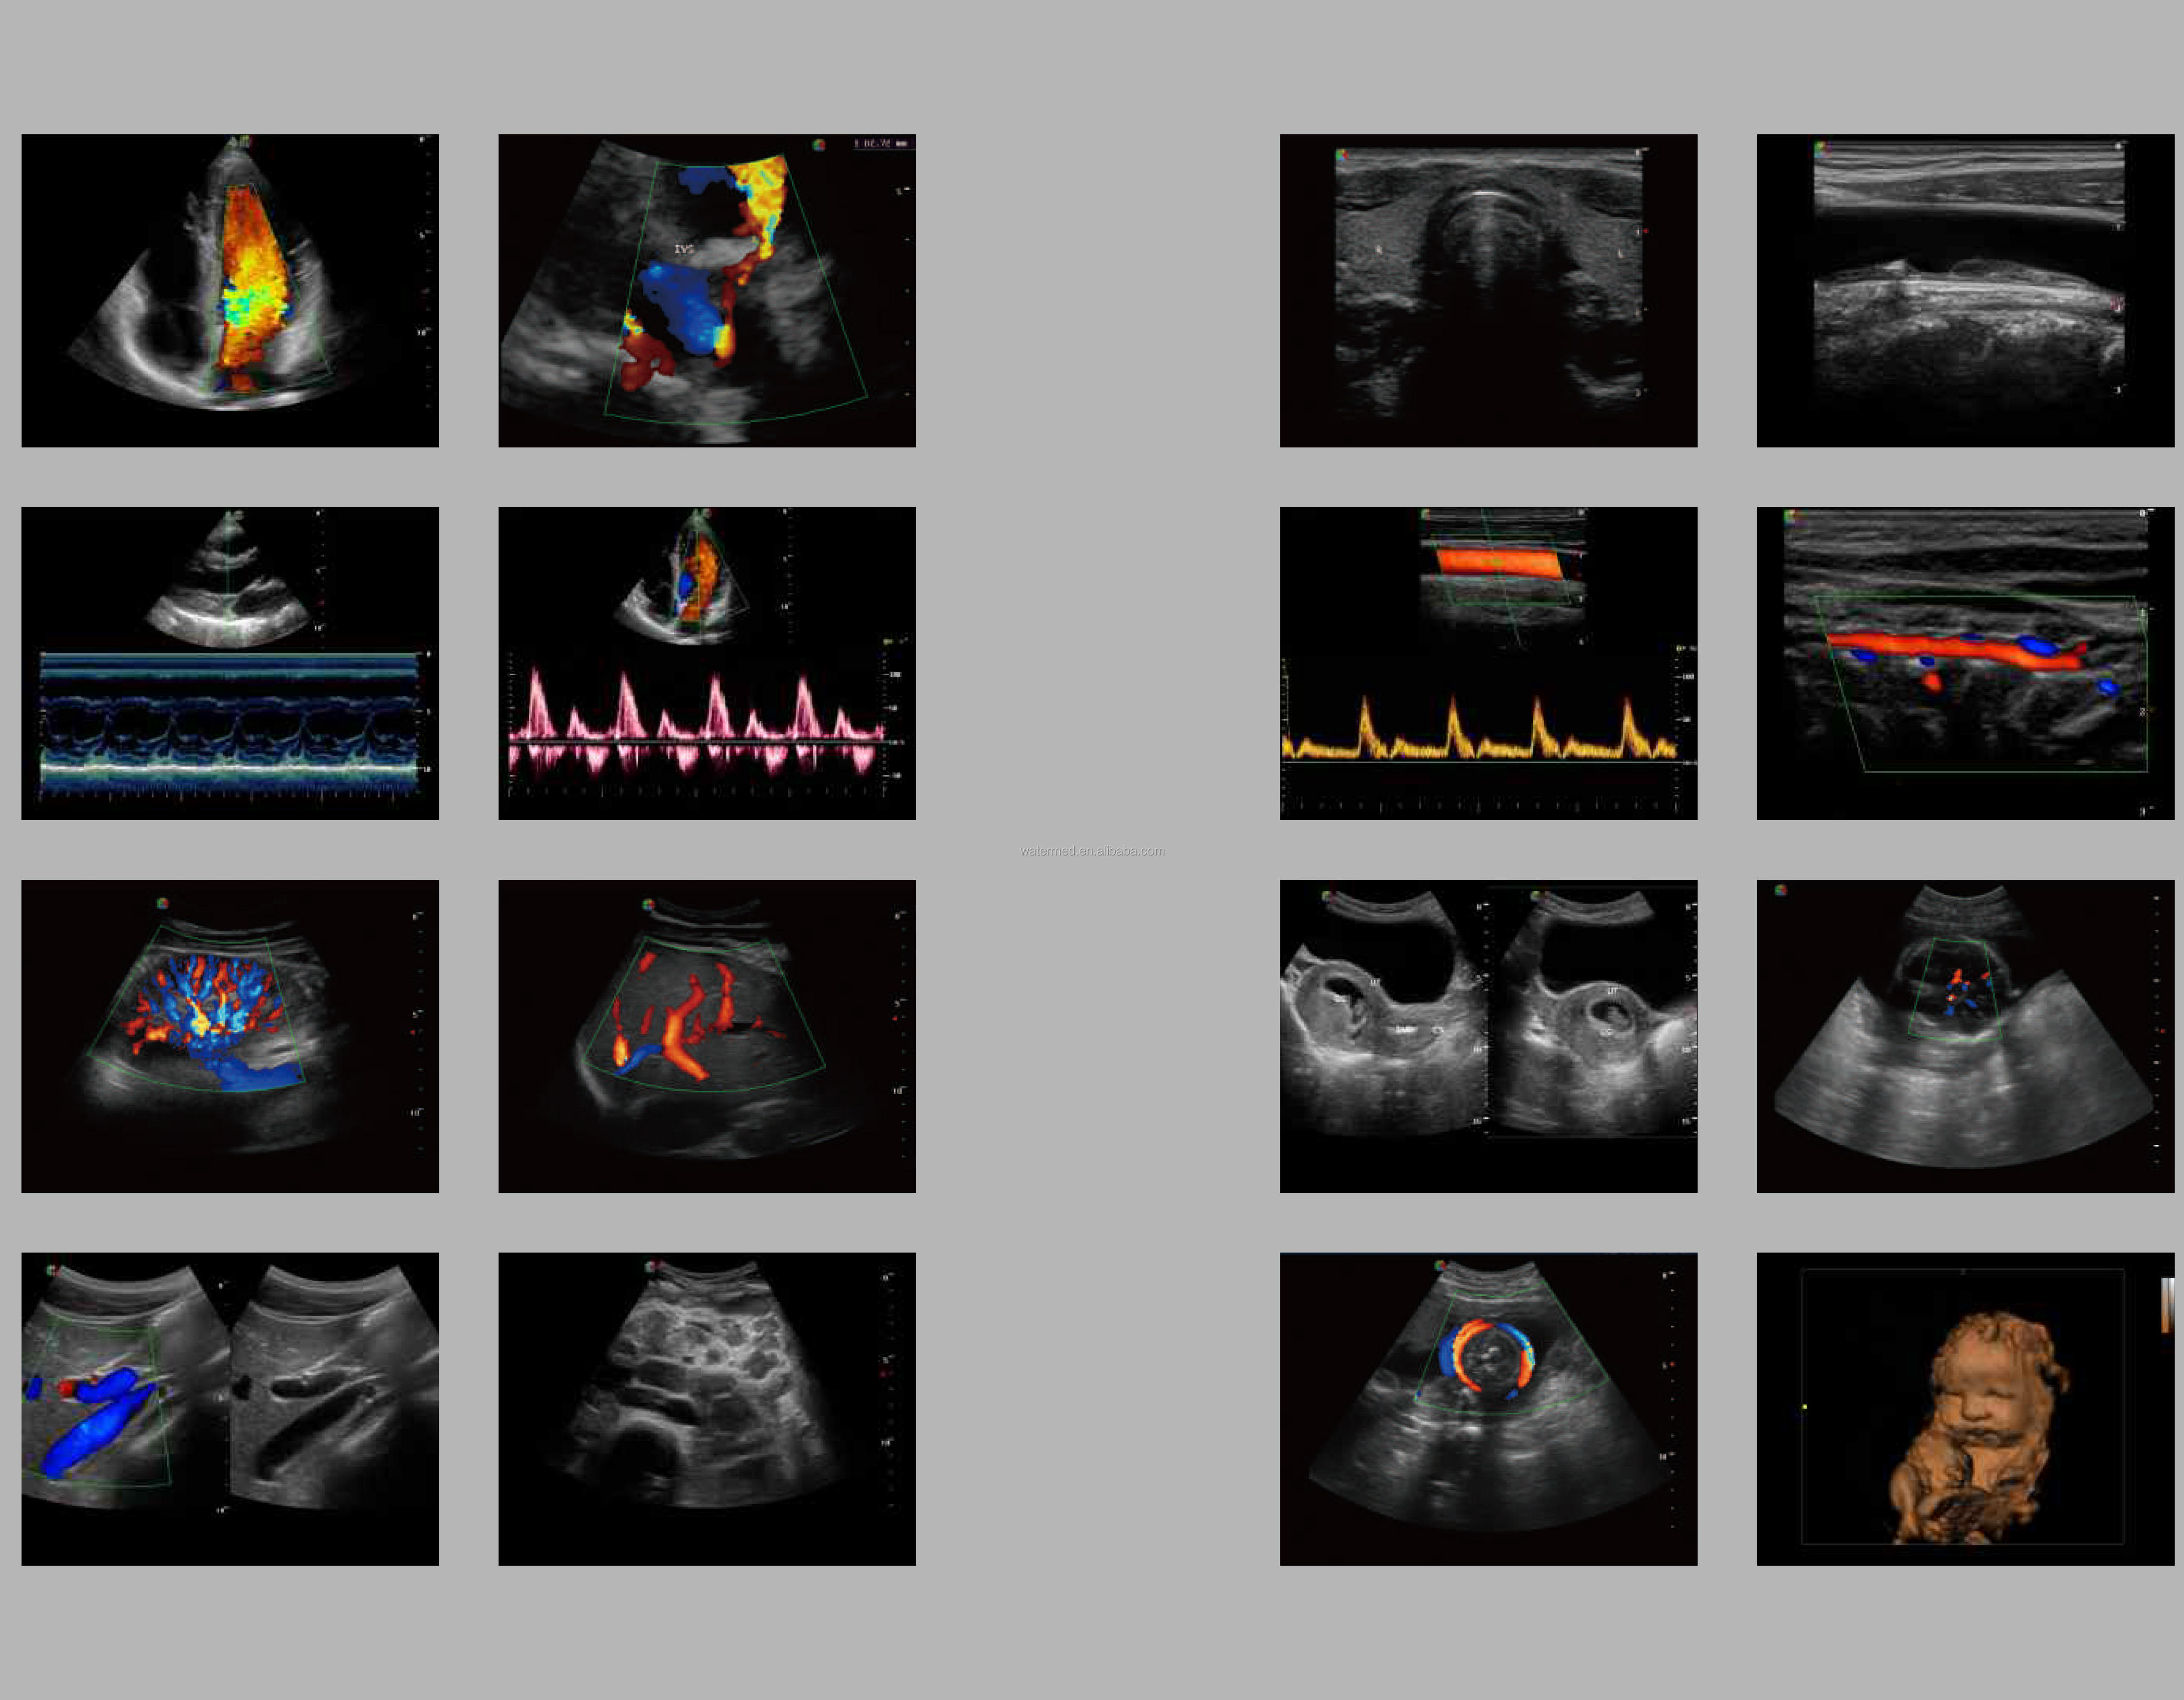

SonoScape has been in the field of ultrasound since releasing the first portable color Doppler ultrasound system. From this dedication, a large number of ultrasound technologies have emerged, especially in hand-held systems. Out of this dedication, the S9 was released as a powerful and versatile imaging platform with a futuristic design. Small in size and wide in application, the S9 is suitable for Cardiology, Radiology, Abdominal, Obstetrics, Small Parts and Urology, providing the best solution for ultrasound imaging with outstanding performance.

spatial composite imaging

Spatial compound imaging utilizes multiple lines of sight for optimal contrast resolution, speckle reduction and boundary detection, the S9 is ideal for surface and abdominal imaging for increased clarity and improved continuity of structures.

pulse inversion harmonic imaging

Harmonic signals are adequately preserved without degrading acoustic information, which allows the S9 to image high-level details and improve contrast resolution by reducing noise and clutter in the visualization of subtle lesions, small sites, blood vessels, etc.

C-Xlasto elastography

SonoScape provides a new method for S9 to support physicians in assessing tissue elasticity. The elastography algorithm detects and visualizes differences in tissue response in real-time through different graphical representations, which is particularly helpful for analyzing breast, thyroid and musculoskeletal structures.

Real-time 3D (4D)

With the addition of physical channels and a new platform, the S9 delivers high-quality imaging and high frame rates to meet the new standard of the SonoScape S series. Thanks to the high frame rate and advanced technology, the S9's 4D imaging can realize the smooth movement of the fetus and provide comprehensive 4D acquisition, data rendering and post-processing functions.

High Density Probe

S9 is equipped with a high-density phased array probe to meet the needs of high frame rate and high resolution for cardiac imaging. Thanks to the high sensitivity of SonoScape color Doppler mapping, the S9 can provide an accurate cardiac diagnosis beyond your imagination.